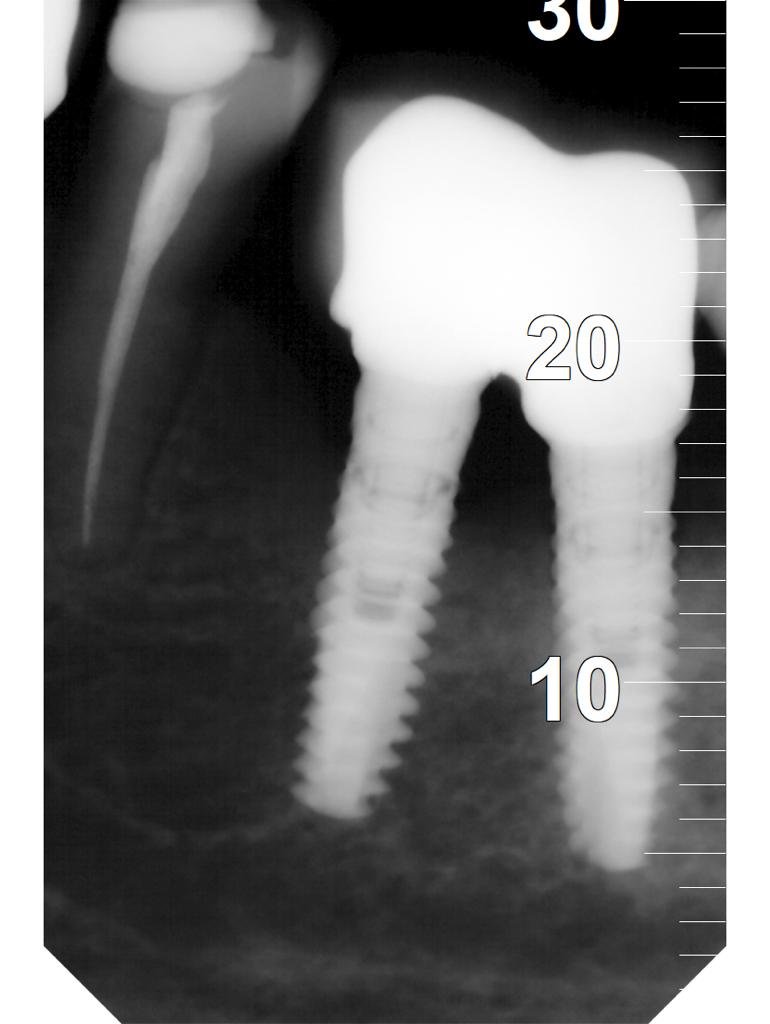

Buenas tardes, El caso que presento es una paciente quien acude a la consulta y presenta implantes colocados en otra clínica desde hacen 3 años. Las rx periapicales muestran un [...]